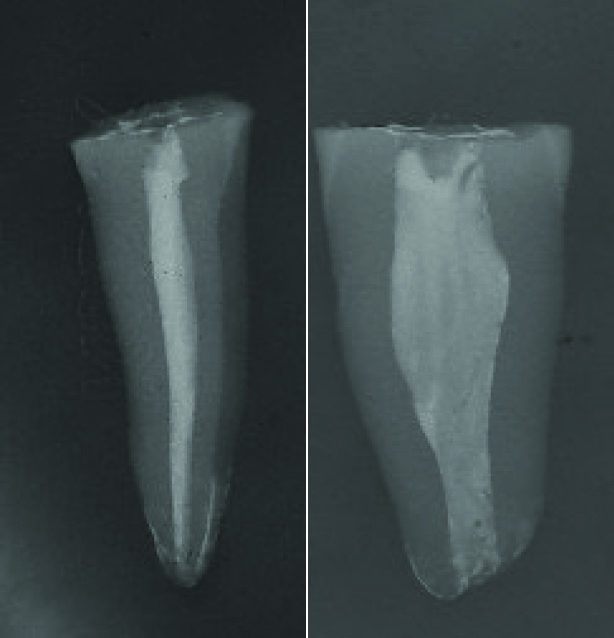

Fig.1 À esquerda radiografia de dente humano extraído, no sentido mesio-distal (mesma visualização obtida em radiografias intrabucais). À direita o mesmo dente em radiografia vestíbulo-lingual.

Para um efetivo preparo biomecânico, a preocupação com a real configuração anatômica do canal radicular está ganhando mais atenção. O acompanhamento clínico e radiográfico é o critério usado para avaliar a qualidade do tratamento endodôntico, incluindo a avaliação longitudinal de sucesso. Com o avanço da tecnologia em imagem, é fácil perceber que as informações aprendidas no passado foram baseadas em um padrão bi-dimensional, dado pelas imagens radiográficas. Entretanto, essas imagens nos dão apenas uma noção bi-dimensional do espaço interno do canal radicular. Atualmente temos ferramentas para obter uma nova realidade, tridimendisional, facilitando a percepção de que a anatomia interna não acompanha a anatomia externa, e que os canais não são cônicos, o que acreditava-se até então, tomando-se por base apenas o padrão radiográfico.

A “Zona V” é a área de extremo achatamento dos canais (figura 3). Essa região não é visível radiograficamente, uma vez que a radiografia nos mostra somente uma visão mesio-distal, e estes achatamentos estão no sentido vestíbulo-lingual.